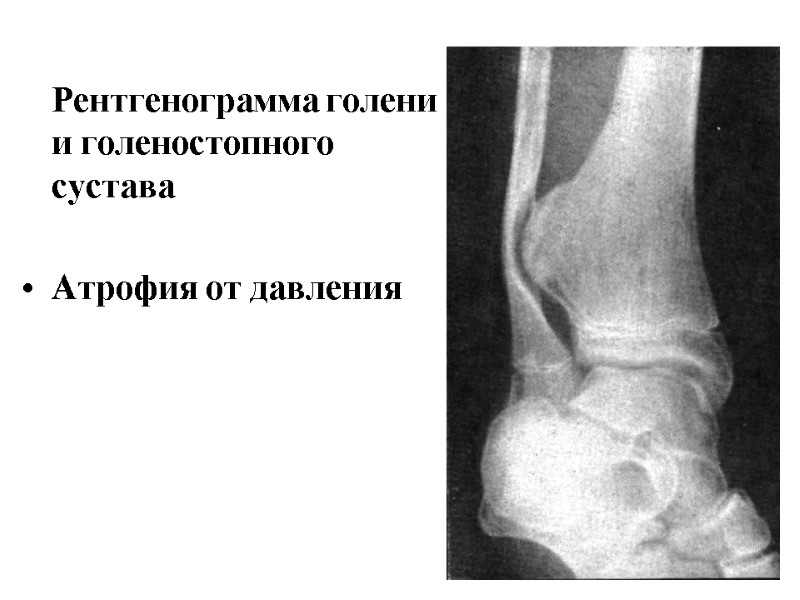

Рентгенограмма голени и голеностопного сустава Атрофия от давления